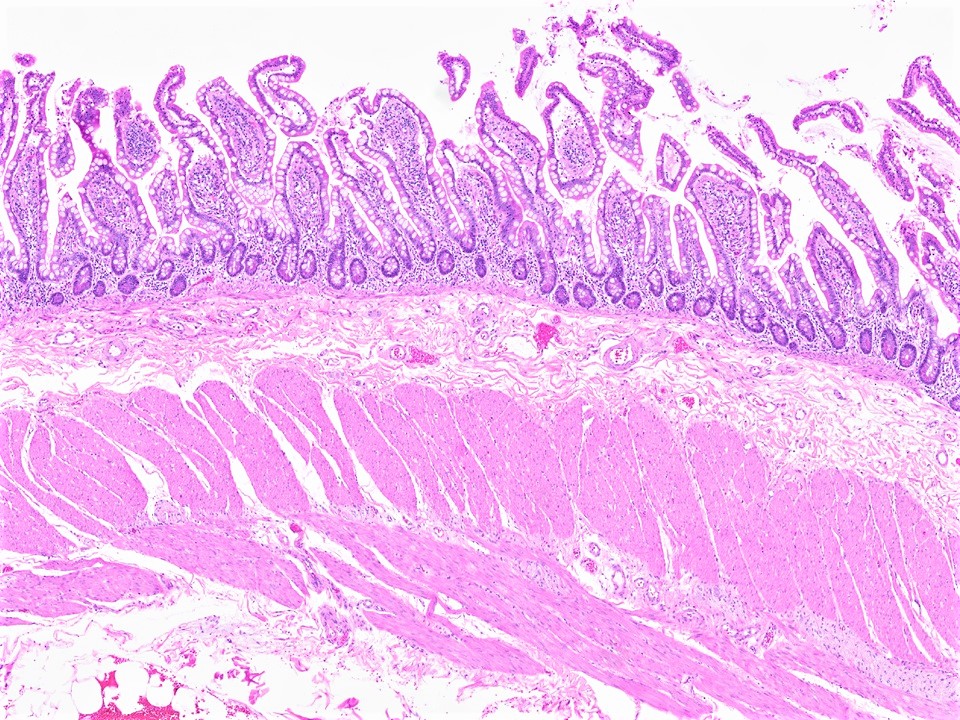

Object: Examination of Histological Slide of Small Intestine

The small intestine is the principal site of digestion and nutrient absorption, extending ~6–7 m from the pylorus to the ileocaecal valve. It is divided into duodenum (25 cm), jejunum (~2.5 m), and ileum (~3.5 m). Its enormous absorptive surface area is achieved through three structural adaptations: plicae circulares, villi, and microvilli (brush border).

- Villi: Finger-like projections of mucosa into the lumen, 0.5–1.5 mm tall, covered by simple columnar epithelium. Each villus contains a central lacteal (lymphatic capillary), blood capillaries, smooth muscle fibres, and a nerve supply. They are tallest in the jejunum and shortest in the ileum.

- Crypts of Lieberkühn: Tubular glands between the bases of villi that extend to the muscularis mucosae. Contain stem cells (base), Paneth cells (base — secrete defensins/lysozyme), goblet cells, enteroendocrine cells, and immature enterocytes migrating upward.

- Lamina Propria: Loose connective tissue filling the core of villi and surrounding crypts; contains capillaries, central lacteals, smooth muscle, lymphocytes, plasma cells, and mast cells.

- Muscularis Mucosae: Inner circular and outer longitudinal smooth muscle — produces villous movement for absorption.

3. Muscularis Externa

Inner circular and outer longitudinal smooth muscle layers with Auerbach's (myenteric) plexus between them for peristalsis.

Distinguishing Features on Slide

- Long villi projecting into the lumen — key distinguishing feature from large intestine

- Crypts of Lieberkühn at villus bases

- Brush border visible at high magnification on enterocyte apex